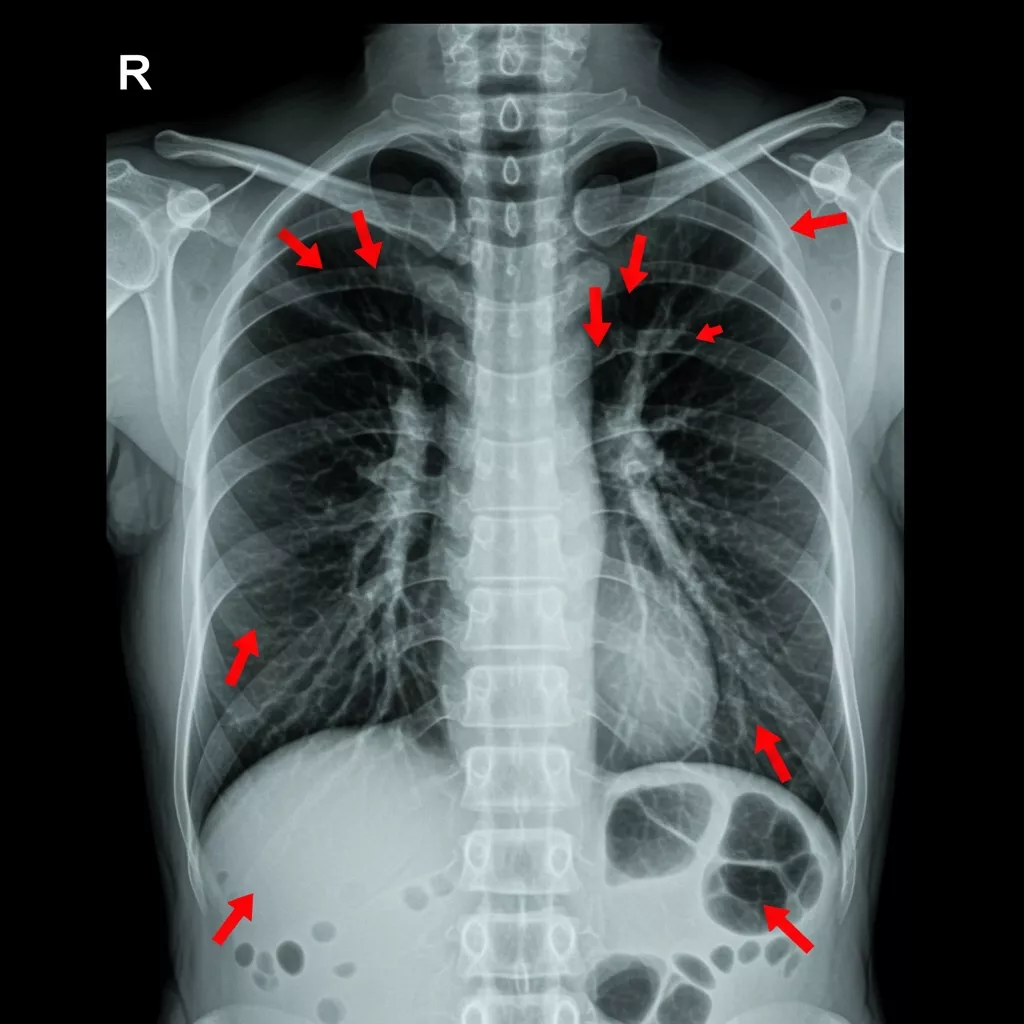

Abnormal Chest X-Ray: Common Findings to Watch For

An abnormal chest X-ray can present a wide range of patterns, each suggesting different potential diagnoses. Understanding these patterns helps clinicians compare normal vs abnormal chest X-ray features with confidence.

1. Consolidation or Airspace Opacity

- Appears as white or opaque areas within the lung.

- Common causes: pneumonia, pulmonary hemorrhage, aspiration.

2. Interstitial Abnormalities

- Reticular or nodular patterns suggest interstitial lung disease, pulmonary edema, or viral infections.

3. Cardiomegaly or Abnormal Heart Contours

- Enlarged cardiac silhouette may indicate heart failure, pericardial effusion, or cardiomyopathy.

4. Pleural Effusion or Pneumothorax

- Effusion: blunted or obscured costophrenic angles with fluid layering.

- Pneumothorax: hyperlucent (very dark) area lacking lung markings, often with visible pleural line.

5. Masses, Nodules, or Calcifications

- Focal lesions may represent tumors, granulomas, or metastases.

6. Abnormal Device Positioning

- Malpositioned central lines, tubes, or pacemaker leads can cause complications requiring immediate attention.

By comparing these findings to the expected anatomy of a normal chest X-ray, clinicians can more easily distinguish clinically significant changes.